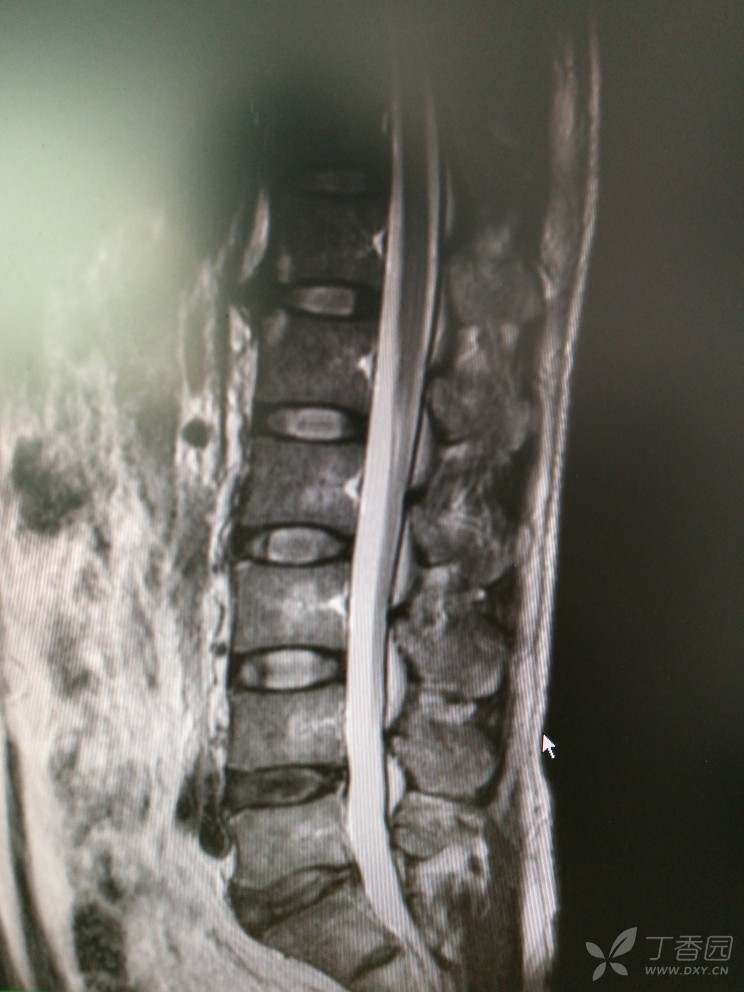

双下肢麻木查因

患者男,46岁,双下肢麻木2年余。

2年前无明显诱因出现双下肢麻木,双下肢沉重感,感觉对称,在坐位、平卧位时发生,活动或抬高下肢后缓解,无双下肢放射痛及乏力等。

查体:腰椎活动可,腰肌稍紧,L2-S1椎无明显压痛,双侧坐骨行程无压痛,直腿抬高试验(-),加强试验(-)肌力5级,肌张力正常,生理反射存在,病理反射未引出。

入院查MRI

我想问还是考虑L4/5 L5/S1椎间盘的变性引起的吗?